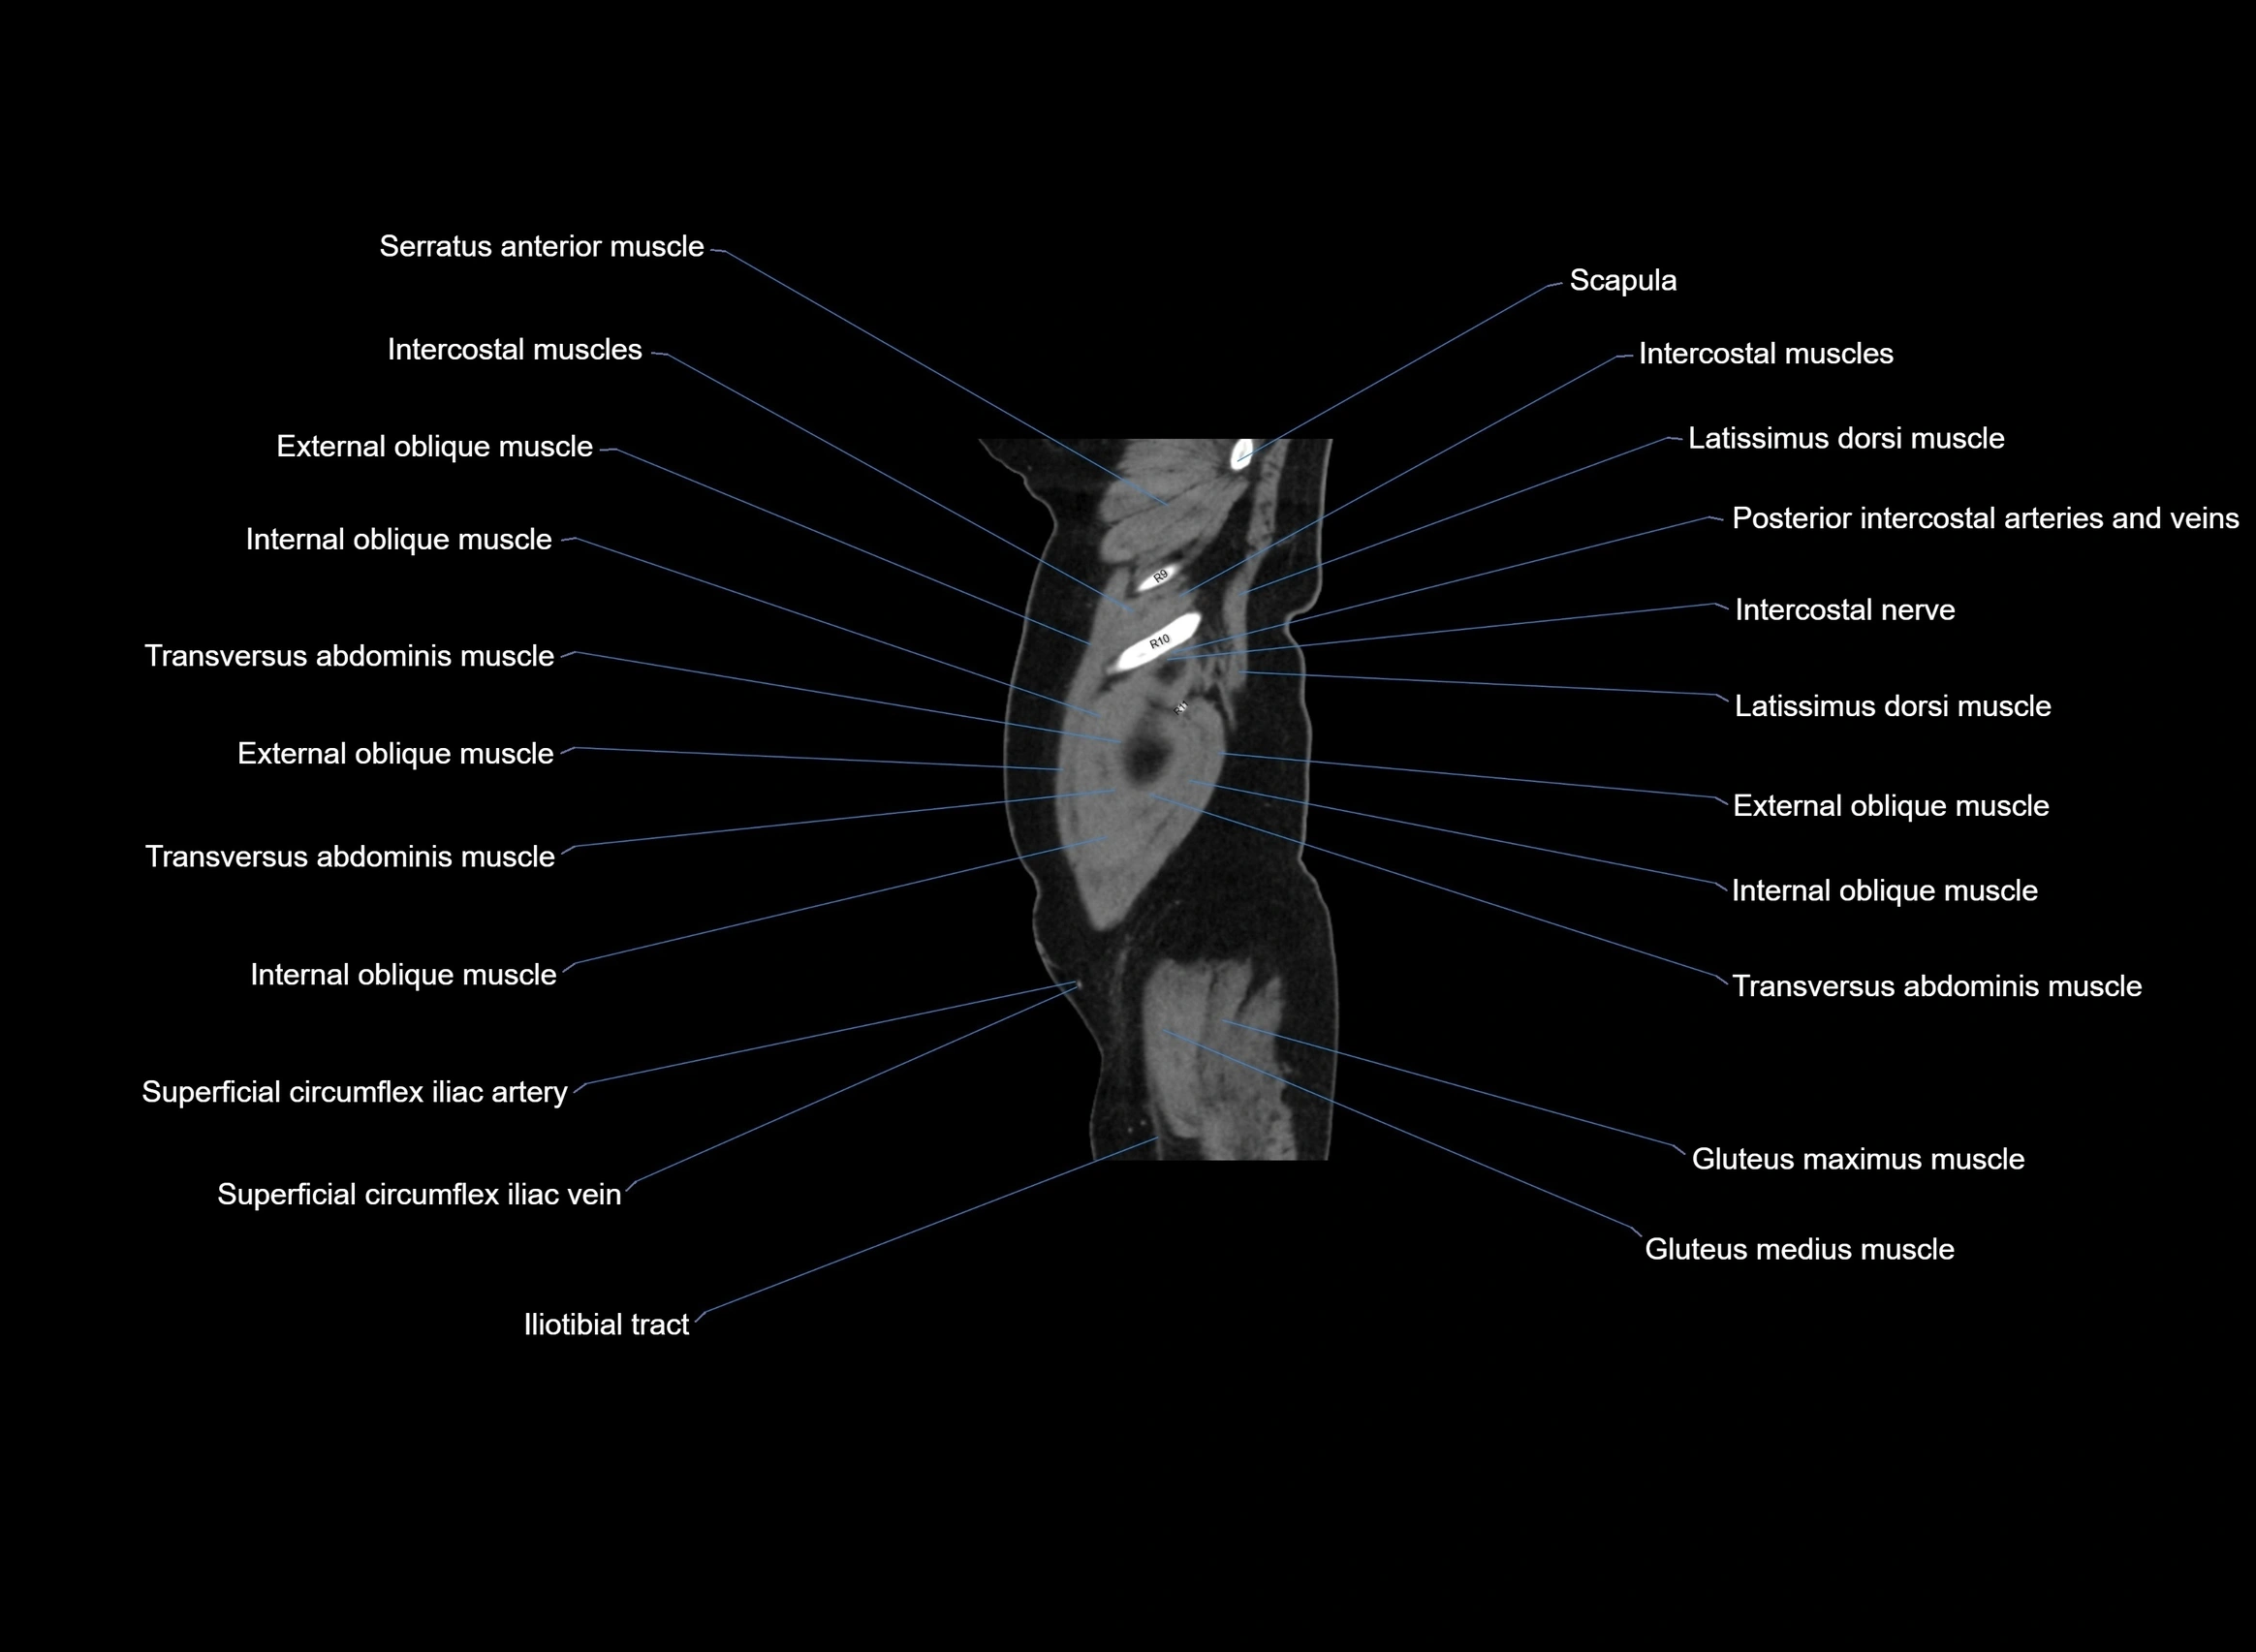

- External oblique muscle

- Iliotibial tract

- Intercostal muscles

- Internal oblique muscle

- Latissimus dorsi muscle

- Superficial circumflex iliac artery

- Superficial circumflex iliac vein

- Transversus abdominis muscle